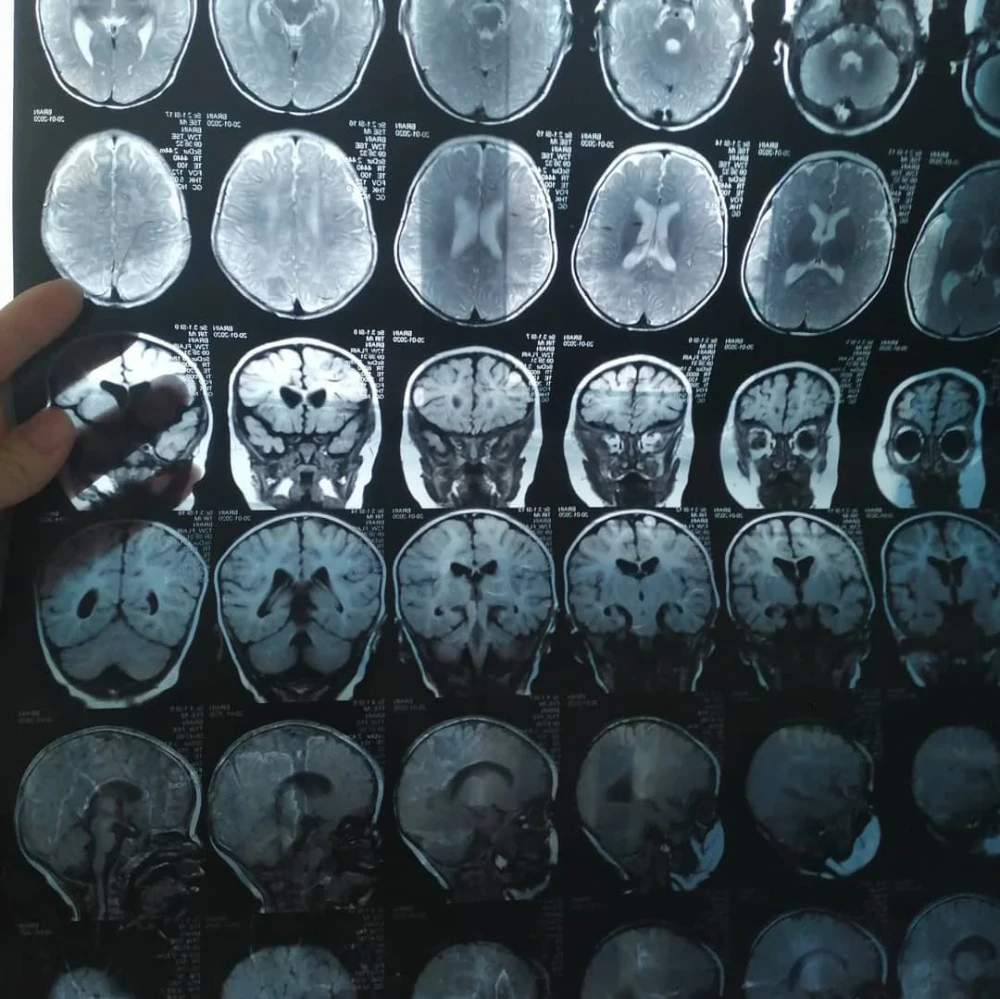

Begimai's daughter has a number of complex diagnoses; she needs help.

Aykol has already undergone two surgeries in Bishkek aimed at correcting the bilateral ankle joint deformity, but the results were not as successful as expected.